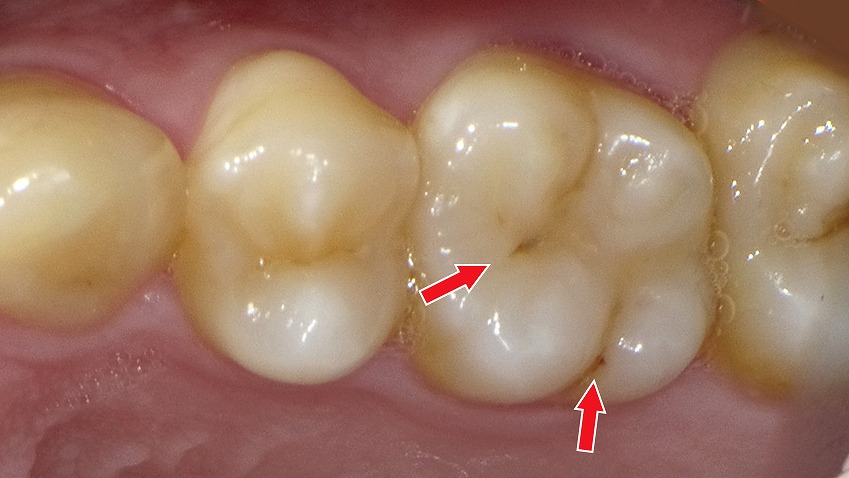

赤矢印が示すように、歯と歯の間(コンタクト部)の初期虫歯は、肉眼ではほとんど確認できません。レントゲンを撮影することで、エナメル質内部の透過像として虫歯を早期に発見できます。見た目に穴がなくても進行している場合があるため、定期的なレントゲン検査は非常に有効です。